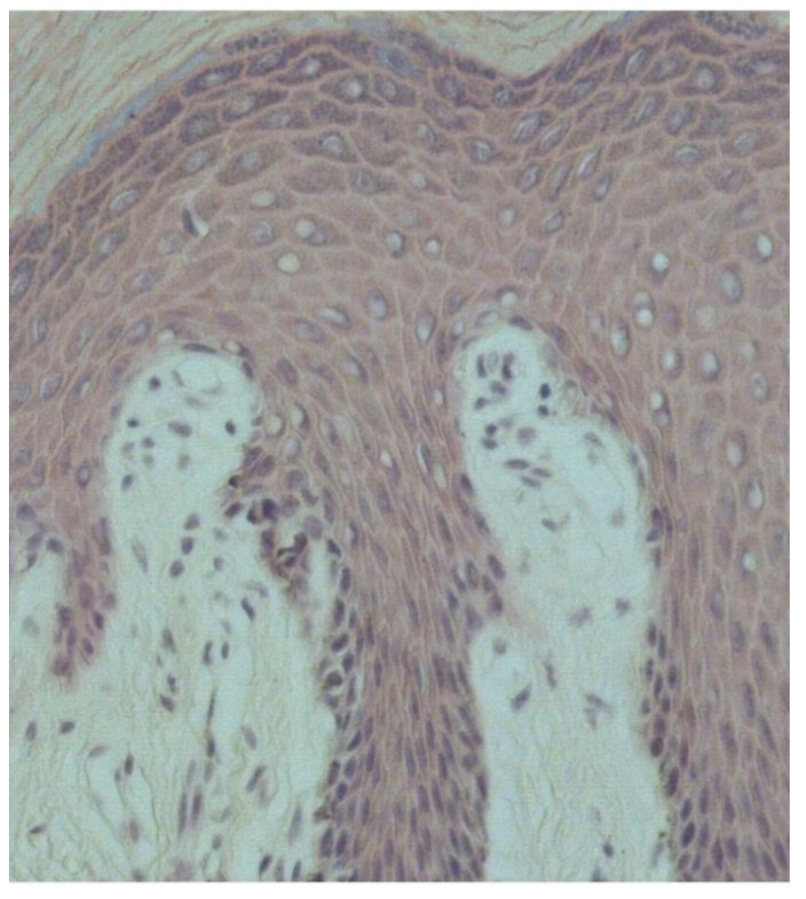

What are identifying features of the different strata of epidermis?

Stratum corneum

- A thick stratified layer of dead keratinocytes

Stratum lucidum

- 1-2 layers of cells undergoing keratinization

Stratum granulosum

- Dark band of cells lining the lucidum and spinosum

Stratum spinosum

- The dense layer of living keratinocytes

Stratum basale

- The basement membrane

What are identifying features of the dermis?

Papillary layer

- Dermal papillae is the connective tissue layer below the epidermal ridges

Reticular layer

- Has dense irregular layer of collagen fibers

Label the 7 points on this slide